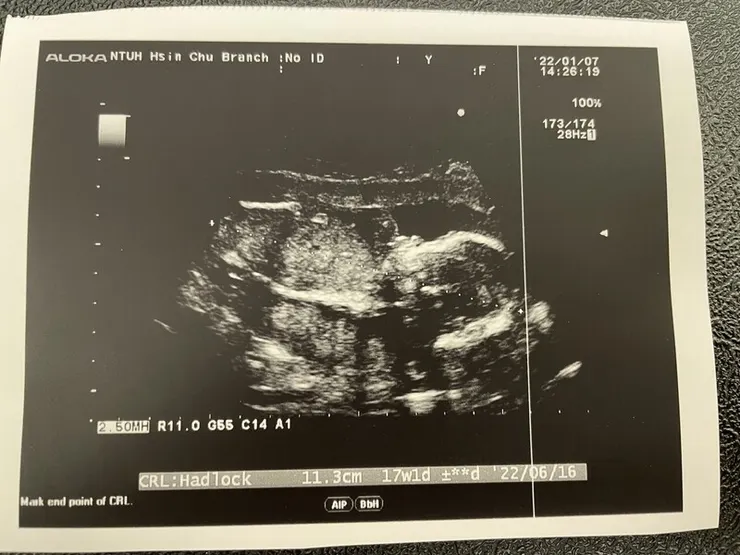

【第17周~性別公開】

哇~~~ 在第17周終於揭曉性別了...

爸爸的前世情人到來!!! 但爸爸的最愛還是媽媽才可以唷XD